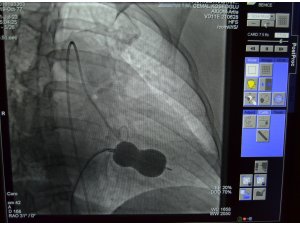

Yapılan işlem ile ilgili açıklama yapan ALKÜ Tıp Fakültesi Öğretim Üyesi Doç. Dr. Cemal Köseoğlu, "Hastanemizde ilk kez uygulanan bu işlemi kardiyoloji birimi hekimleri olarak birlikte değerlendirdik ve mitral balon yardımıyla işlemi yapma kararı aldık. Hastamız Behice Hanımı, Anjıyo ünitemizde hiç uyutmadan mitral balon yardımıyla ile kasıktan girerek daralmış kapağını bir buçuk saat süren işlem sonunda açtık. Son kontrollerimizi yaptık. Hastanın kalp kapağı gayet güzel çalışıyor. 2 gün yoğun bakımda takibi sonunda taburcu işlemlerini gerçekleştireceğiz" ifadelerini kullandı. Doç. Dr. Köseoğlu; tıp teknolojisindeki gelişmeler ve giderek artan ameliyatsız müdahale imkanları ile çok ciddi kapak müdahalelerini çok düşük risklerle yapabilme olanağı bulduklarını da sözlerine ekledi.